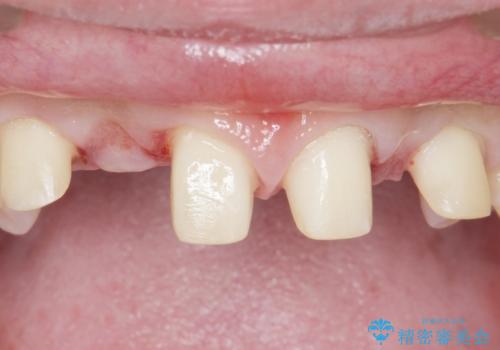

- 生まれつき上の側切歯と犬歯が逆に生えていることを主訴に来院された患者様です。

他院で矯正を行っていたそうですが、なかなか終わらないため途中で治療をやめてしまったとのことでした。

矯正以外の治療法で早く治したいとのご希望により、上顎両側犬歯を抜去しオールセラミックのブリッジによる補綴治療を行いました。